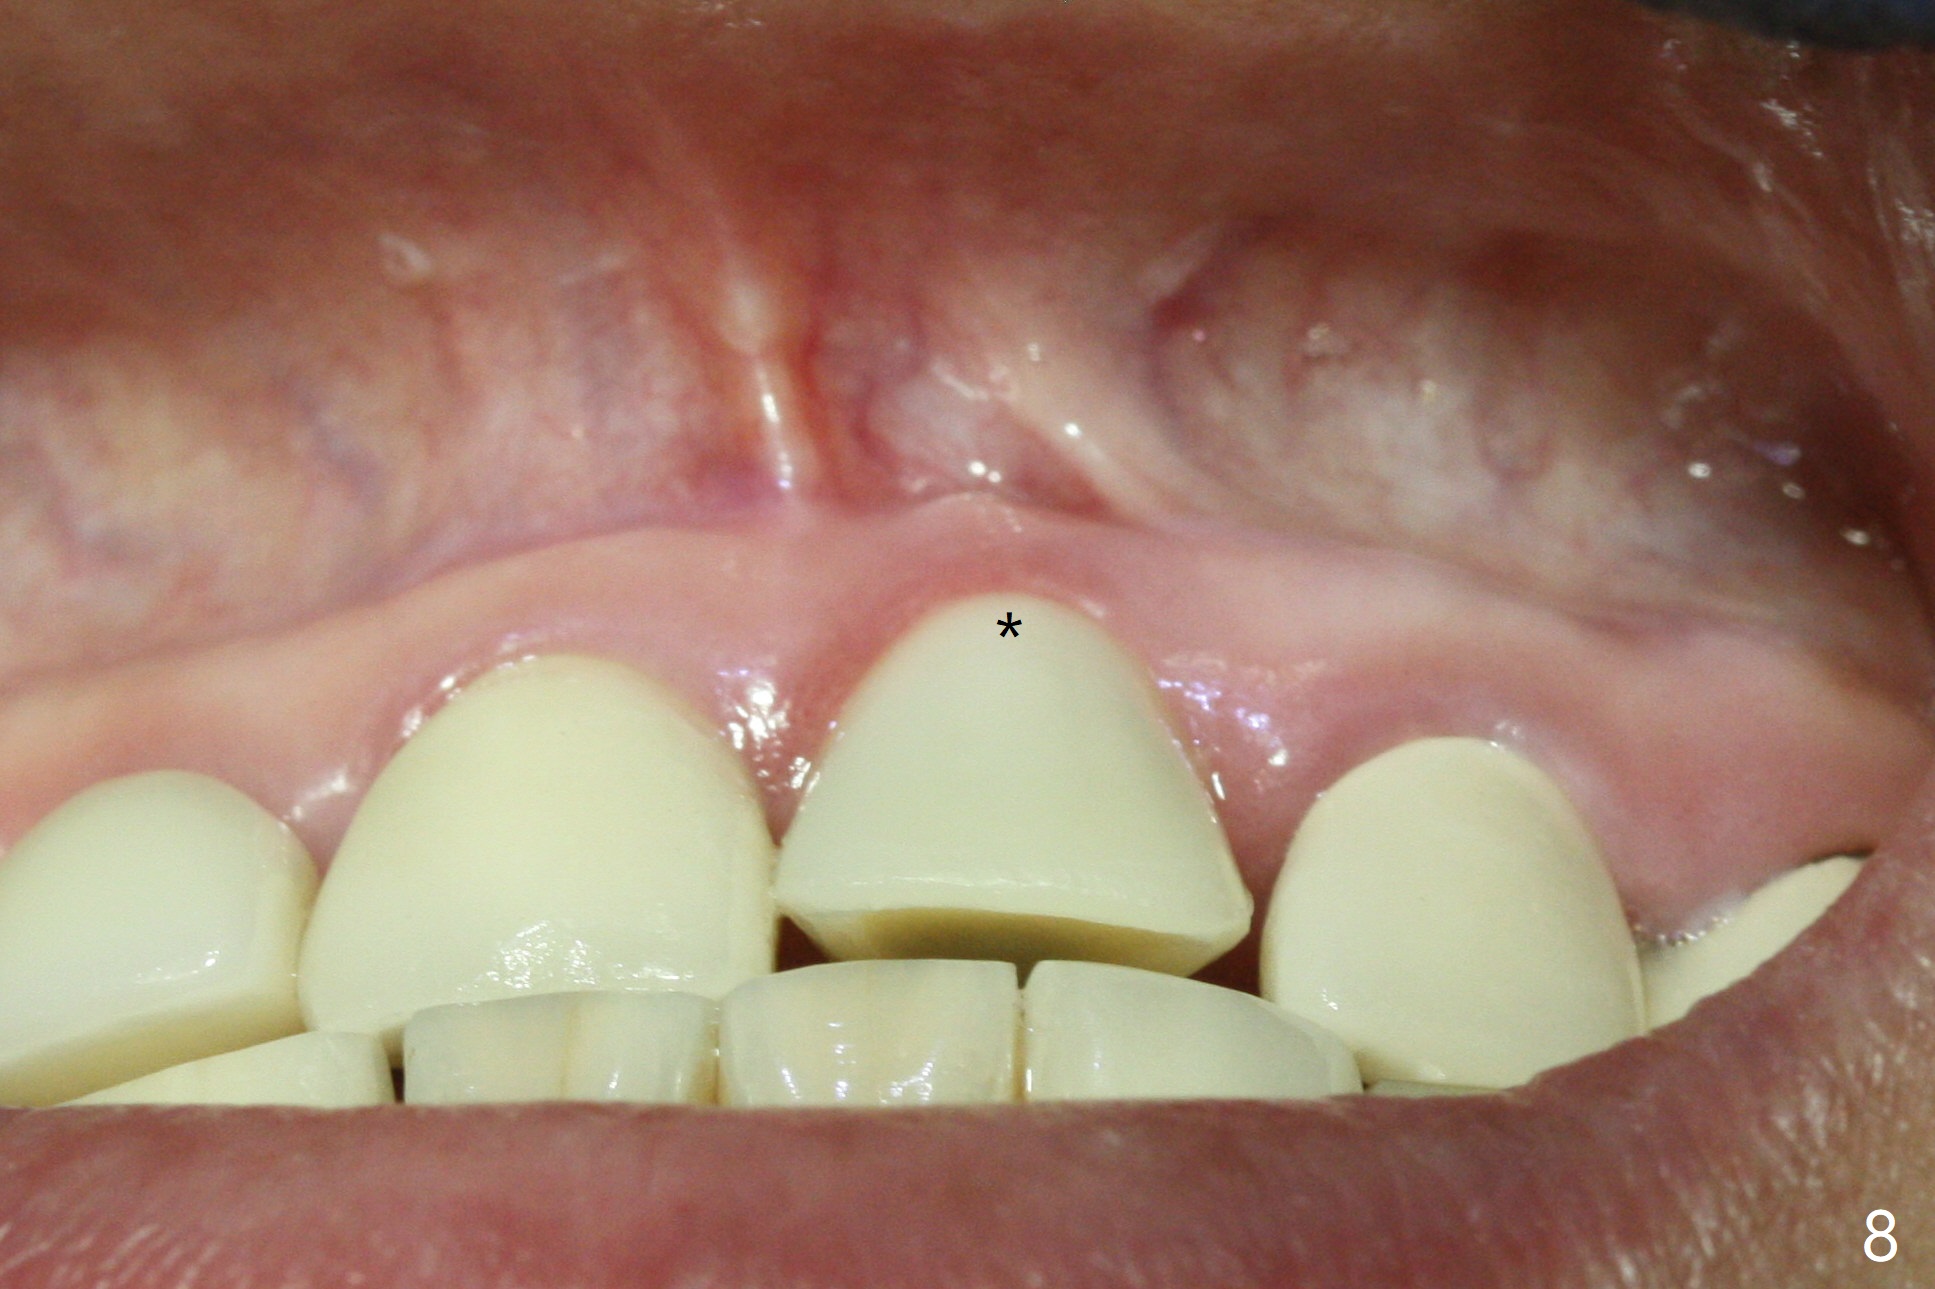

The buccal contour at #9 seems to be slightly concave preop (Fig.1,2 (*)). In fact the buccal plate is found to be lost when the tooth is extracted. Osteotomy is initiated as palatal as possible apical, but the occlusion dictates the coronal end of the osteotomy should be buccal, leaving the buccal gap ~ 2 mm for bone graft. The initial osteotomy (18 mm deep) appears to be close to the Incisive Foramen (Fig.3 blue dashed line). The nasal floor appears to be intact when the drill is removed. Subsequent osteotomy is adjusted so that the apical end of the osteotomy moves distal; when a 3.8x15 mm dummy implant is partially placed, there is clearance (Fig.4). It remains so when a definitive implant is seated (Fig.5); Vanilla graft is placed (Fig.5 *) before placement of a 4.5x5.5(3) mm abutment. More allograft is placed when an immediate provisional is fabricated (Fig.6 arrow and *). The gingiva remains to be recessive 1 month postop (Fig.7). It seems to be related to the bulky gingival margin of the provisional (Fig.8 *). After trimming the latter (Fig.9 *), the gingival margin immediately returns close to normal (Fig.10). The gingival margin is even between #8 and 9 two months postop, but the bone graft is exposed apically (Fig.11 ^). It may heals by itself. Otherwise debridement, regraft, PRF and suture are pending. The coronal portion of the socket heals 4 months postop (Fig.12). The gingival cuff forms by the immediate provisional (which is removed for impression) 4 months postop (Fig.13 *). While the full Zirconia crown at #7 remains intact (Fig.14), the PFM at #9 has porcelain chip (Fig.15). It is partially due to the occlusion; while the crown at #7 has clearance with the opposing dentition (Fig.16 *), the one at #9 has no. The access hole at #9 (Fig.17 *) seems to weaken the crown structure. There is no access hole at #7. No solid posterior support is another contributing factor for chip (Fig.18). The buccal plate has mild atrophy at #7 and 9 (Fig.19 *). A piece of bone graft is being expelled apically at #9 (Fig.20 >) and is removed subsequently (Fig.21). Before impression for repacking porcelain, the opposing incisal edge has been shortened (Fig.22 arrows, as compared to Fig.16). Since the ideal access hole is at the incisal edge (Fig.25 black circle), buccal to the existing one (Fig.24 A), the abutment is torqued before the repaired crown is recemented (Fig.23). Finally the crown has occlusal clearance (Fig.26). Porcelain chips again around the access hole of PFM 1.5 years post 2nd cementation. The dense bone at the crest (*) cannot explain why the abutment is not loose, since it remains incompletely seated (>). As it was trimmed short, an angled abutment is used (Fig.28). The coronal end is lingual, while #9/24 is edge to edge. The lingual aspect of the coronal end of the abutment is heavily trimmed to reduce bulkiness. To prevent chip, Zirconium crown will be fabricated in spite of the fact that it does not match the PFM of #8 (potential shade discrepancy). The patient is pleased with the new Zirconia crown (Fig.29).